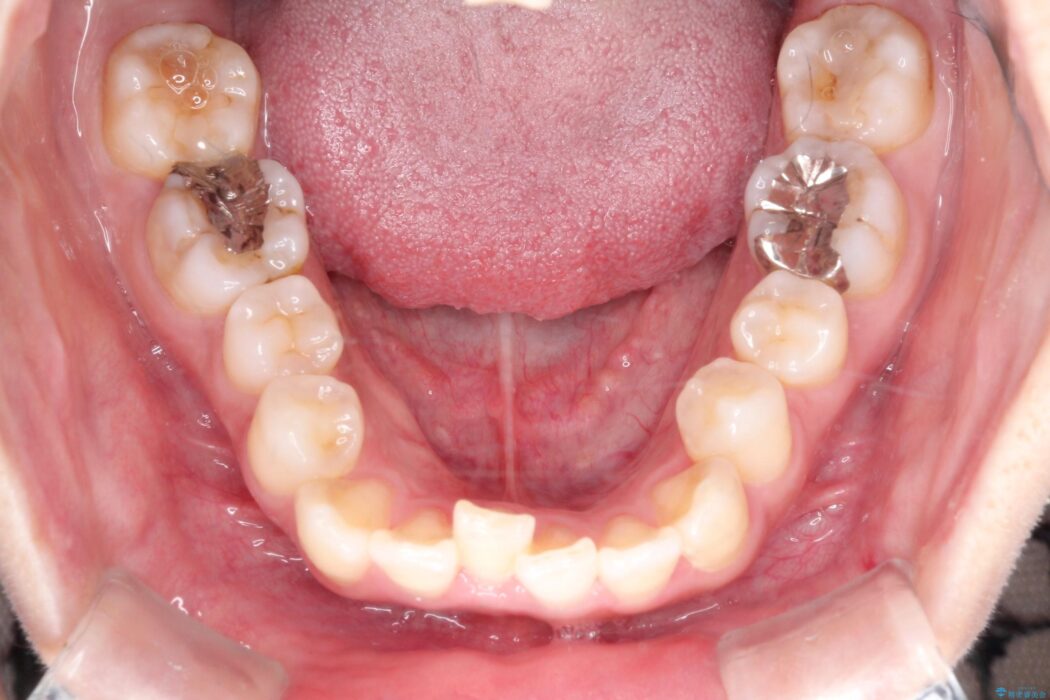

口元を下げて前突感を無くしたい、下の歯の凹凸も無くしたいとご来院された患者様です。

アゴの骨格的なズレがあったため、歯の真ん中を完全に合わせることは不可能と説明。上下4本抜歯を行い、ワイヤー矯正で噛み合わせの大きな改善を目指しました。